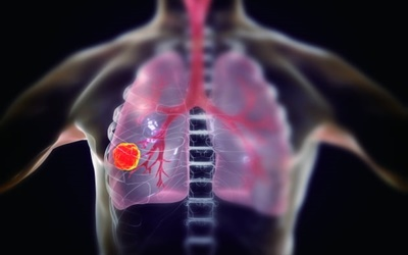

이번 기사에서는 폐암 초기 증상에 대해 자세히 정리해 알려 드리겠습니다 . 폐암은 국내암 사망률 1 위로, 과거에는 흡연이 폐암의 주된 원인 이었지만 , 현재는 비흡연 폐암 환자도 대폭 증가했습니다 . 폐암은 의학 기술로 발달하여 생존율이 높아지고 있습니다 . 폐암의 초기 증상은 무엇인가를 알아보겠습니다.

폐암의 초기 증상